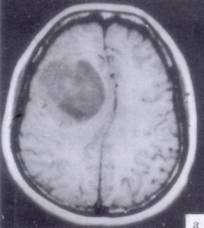

问题 病历摘要:??患者男性,52岁。头痛伴呕吐2月,呕吐呈喷射性。既往身体健康。体检:神清,表情淡漠,反应迟钝,双眼底视神经乳头明显水肿,左鼻唇沟稍浅,左腹壁反射减弱,左上下肢肌力4级,左Babinski征(-)。 为明确诊断,可申请哪些辅助检查?

选项 A.内分泌功能检查 B.脑电图 C.头颅平片 D.头颅MR E.TCD F.SPECT G.CT H.PET

答案 DG